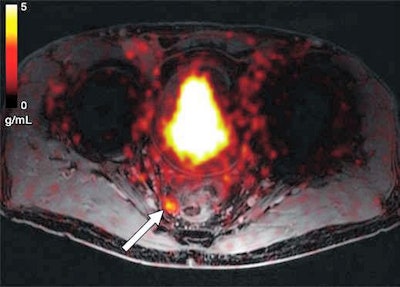

Axial Ga-68 PSMA-fused PET/MR image shows abnormal radiotracer uptake (arrow) within rounded right mesorectal lymph node. Transrectal biopsy findings were negative for malignancy. Patient underwent androgen deprivation therapy. Image courtesy of AJR.On a per-patient basis, the mean sensitivity reached 89%, and the PPV was 90%. On the other hand, specificity was rather low at 31%, and the negative predictive value was 25%.